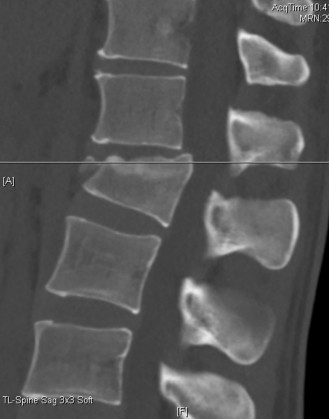

The correct answer is (A). As the case scenario strongly suggests an injury to the spine at the thoracolumbar junction, a CT scan of both the thoracic and lumbar regions is indicated. An MRI should not be the first imaging study obtained. Standing films should not be obtained in a trauma patient with a potentially unstable spine injury. A CT myelogram would only be obtained if an MRI was indicated but the patient had a contraindication to an MRI. Images of the above patient are shown inFigures 1–25 and 1–26. This injury is best characterized as which of the following? 1. Compression fracture

Figure 1–25

Figure 1–26

The correct answer is (B). The images demonstrate an L1 vertebral body fracture with a small degree of kyphosis. There is comminution of the vertebral body with a posterior vertebral body fragment that is slightly retropulsed into the spinal canal. This separate posterior vertebral body fragment (which is noncontiguous with the pedicles) is the hallmark of a burst fracture. Compression fractures do not have any posterior vertebral body involvement. A Chance fracture, also known as a seat belt fracture or flexion–distraction injury, will exhibit distraction of the posterior elements through bone, bone-ligament, or purely ligament structures, with an axis of rotation somewhere within the anterior vertebral body or anterior to the vertebral body. A fracture dislocation exhibits translational deformities between the injured levels. While there appears to be a translational deformity on the sagittal CT, the vertebral bodies of the uninjured levels above and below are actually well aligned.